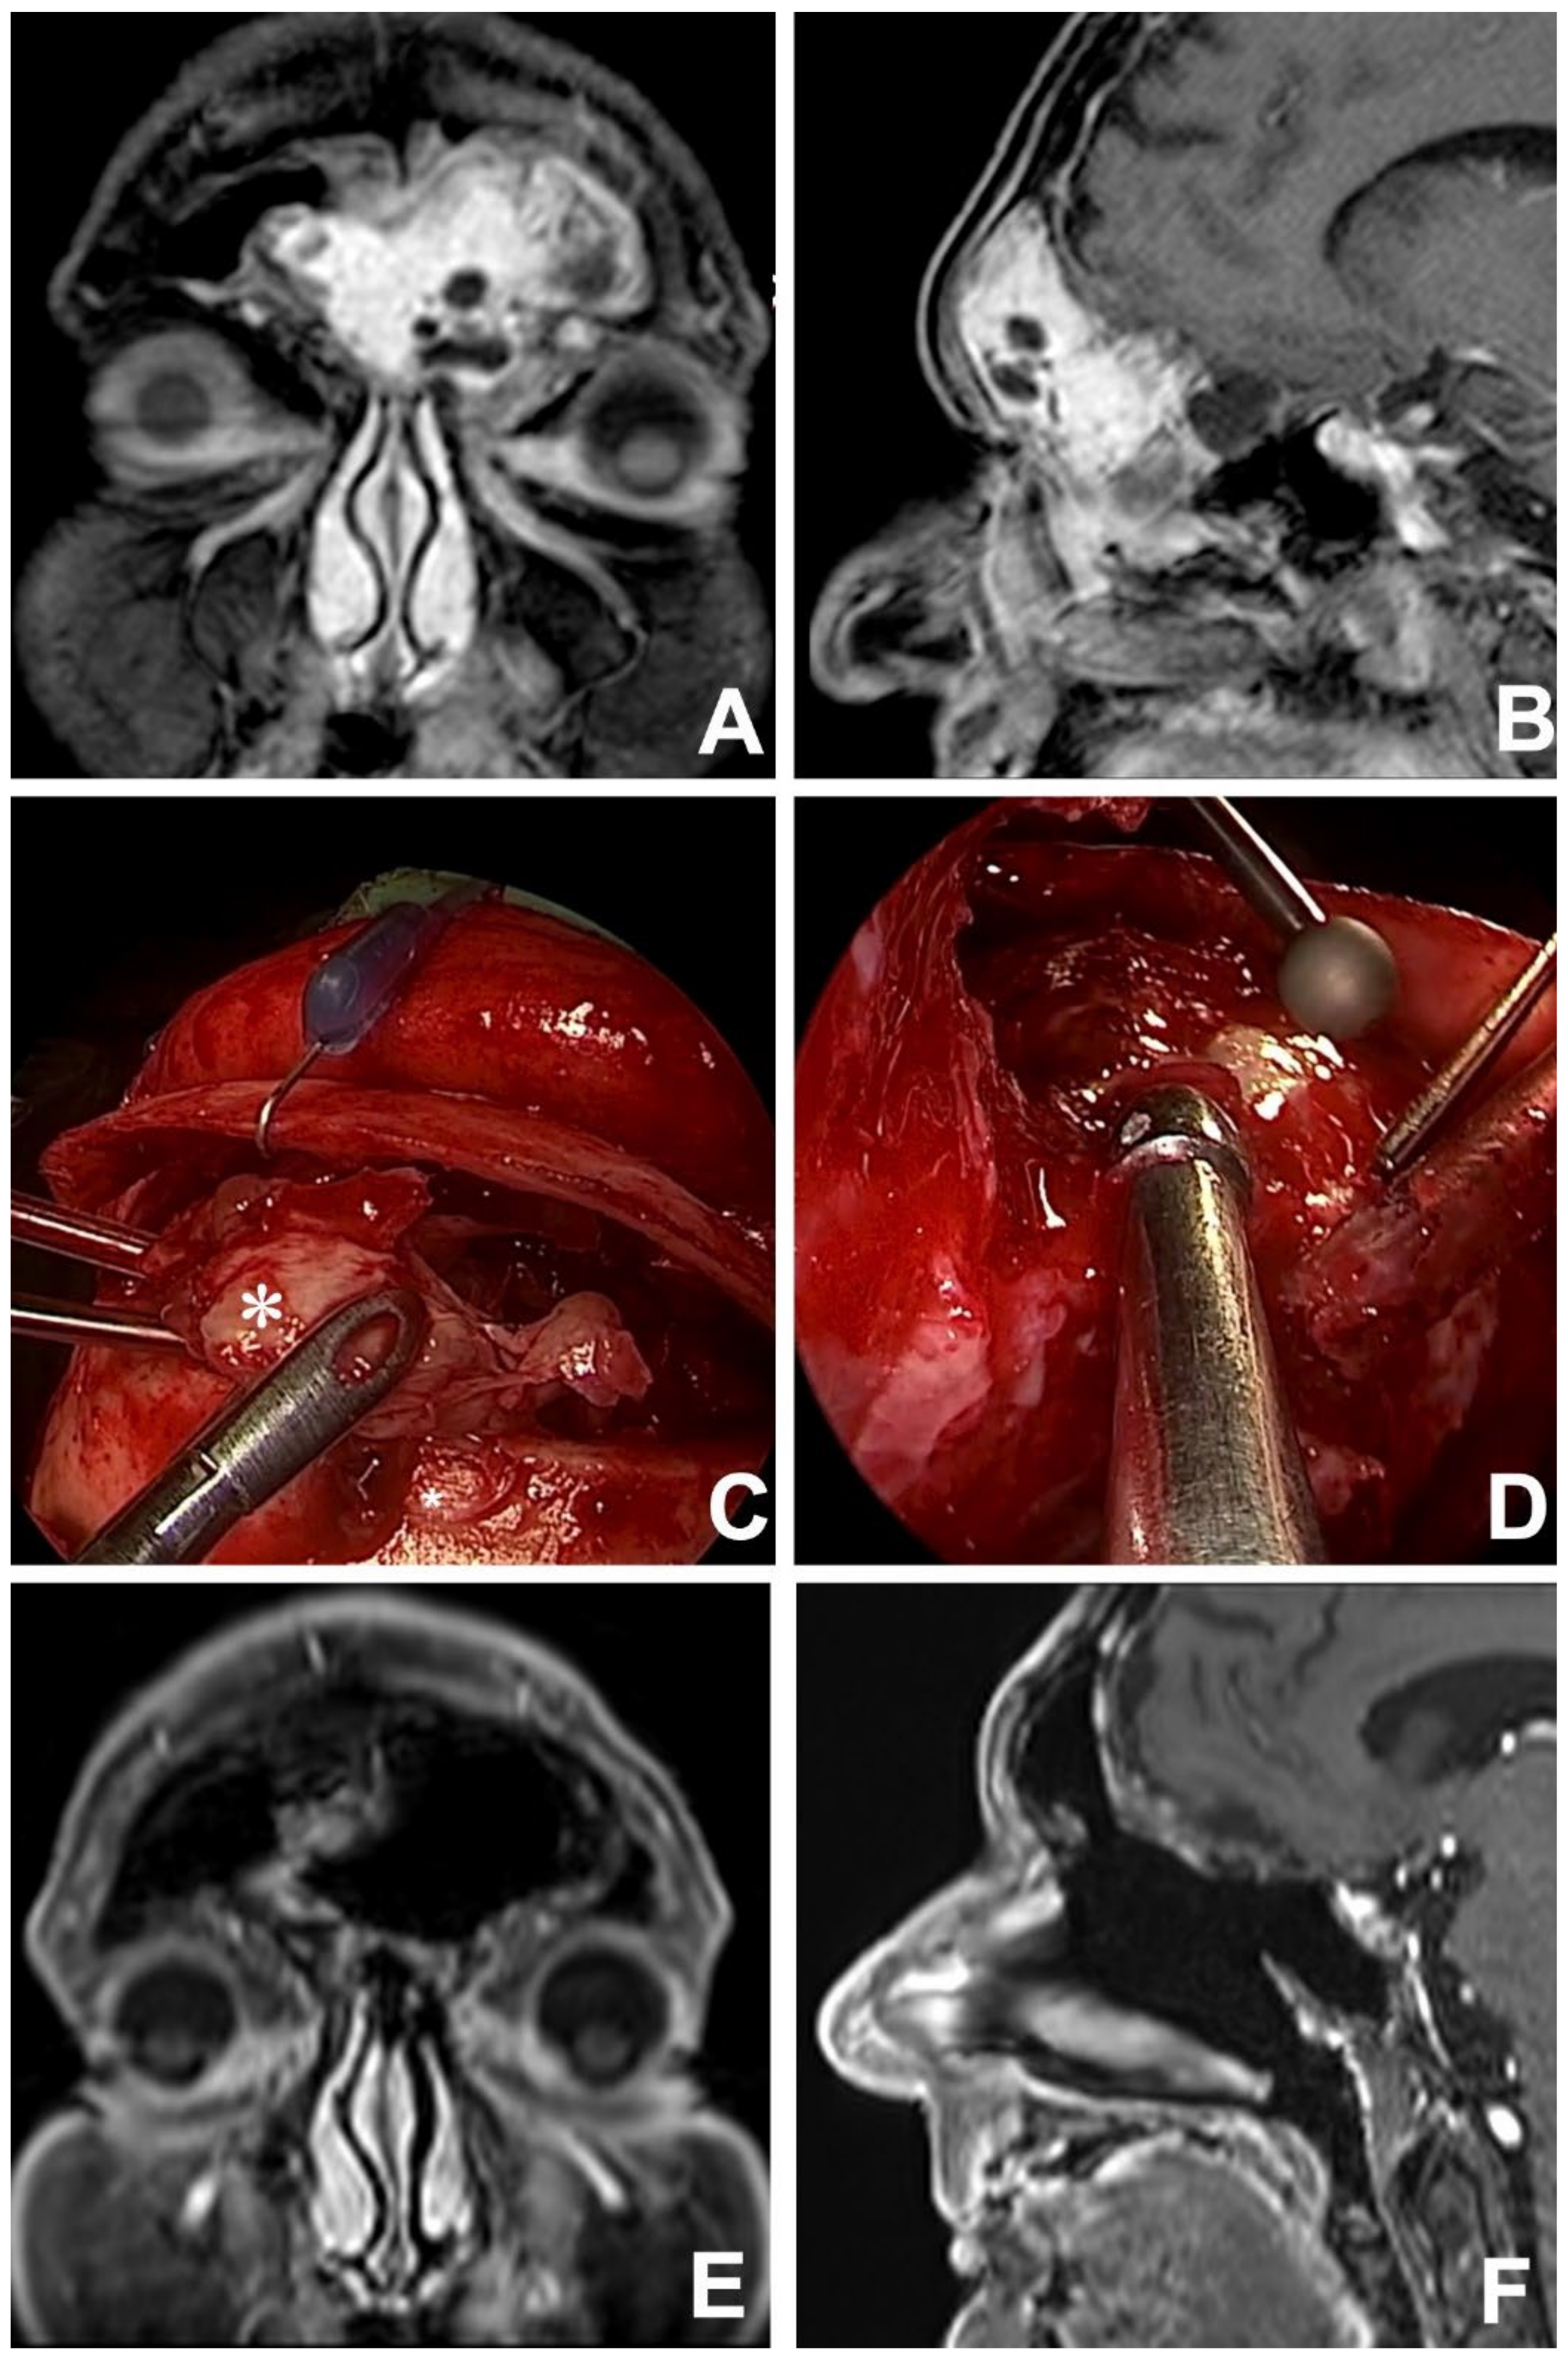

Figure 3. Contrast-enhanced MRI in coronal (A) and sagittal (B) views showing a left frontoethmoidal INI-1 deficient squamous cell carcinoma. After 3 cycles of induction chemotherapy (TPF regimen) an MRI in the coronal (C) and axial (D) view revealed an incomplete response. Tumor persistence was resected via a combined approach: endoscopic transnasal and osteoplastic flap (E), with an exposition of anterior cranial fossa dura (*) which appeared to be free from tumor infiltration (F). At 12 months, postoperative contrast-enhanced MRI in coronal (G) and axial (H) views revealed no local recurrence.

Diagnosis is made on imaging studies such as computed tomography (CT) and magnetic resonance (MR), which should precede biopsy, which is mainly performed via a minimally invasive approach (i.e., endoscopic transnasal approach), in order to define the histological profile of the cancer before planning the definitive treatment. This should be recommended in clinical practice since nowadays histotype has proven to be one of the main determinants of prognosis and essential to establishing the most appropriate multidisciplinary treatment strategy [5,7,8]. In this regard, the slightly better oncologic outcomes observed in the present cohort, compared to the observation by Bhojwani et al. [1], with a five-year DSS of 62.6%, might be in part explained by the implementation of histology-driven multimodal strategies in the management of such cancers, especially in locally-advanced and poorly-differentiated neoplasms (Figure 3).